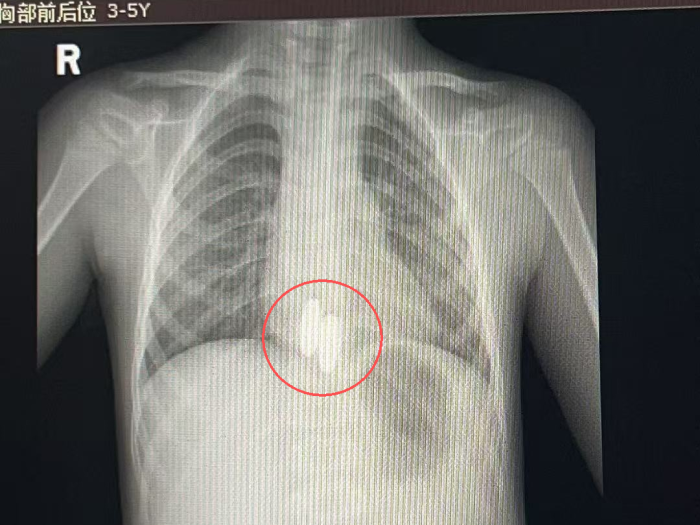

接诊的消化内科主治医师李燕玲介绍:“磁力珠具有强磁性,若在胃内相互吸附或进入肠道,可能导致肠梗阻、穿孔甚至危及生命。”经X线检查后确认,两颗磁力珠已滑入患儿胃部,需立即通过胃镜取出。

X线影像下清晰可见误吞的磁力珠